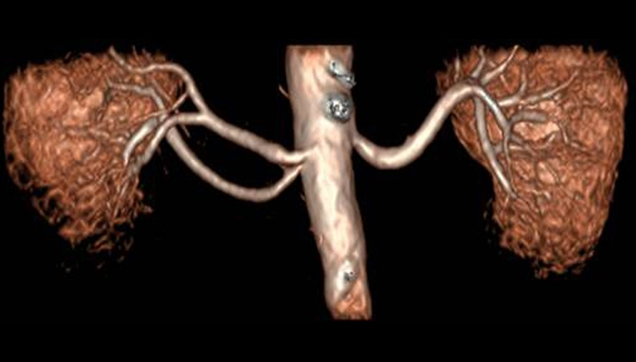

somos uno de los pocos centros privados que actualmente dispone de un equipo de Resonancia Magnética para realizar estudios cardiovasculares, una técnica de última generación para la evaluación de pacientes con cardiopatías, y de la tecnología más avanzada para realizarlos (equipo RM de alto campo, antena específica para estudios cardíacos, software avanzado de reconstrucción de imágenes en 3D y grabación de CD e impresión de imágenes a color).

Por primera vez en Guadalajara le presentamos las nuevas secuencias 3D para estudio de las arterias coronarias por cardio-RM, las cuales permiten obtener imágenes resolutivas de sus segmentos proximal y medio, sin la necesidad de utilizar contraste paramagnético, de utilidad para la práctica clínica.

Las principales ventajas de nuestro nuevo cardio-RM son la ausencia de radiación ionizante así como de contrastes yodados. La posibilidad de estudiar las arterias coronarias en el momento actual, culmina el concepto de “todo en uno” ( one stop shop) como la técnica que puede valorar en un solo estudio todo el espectro anatómico y funcional de la cardiopatía isquémica.